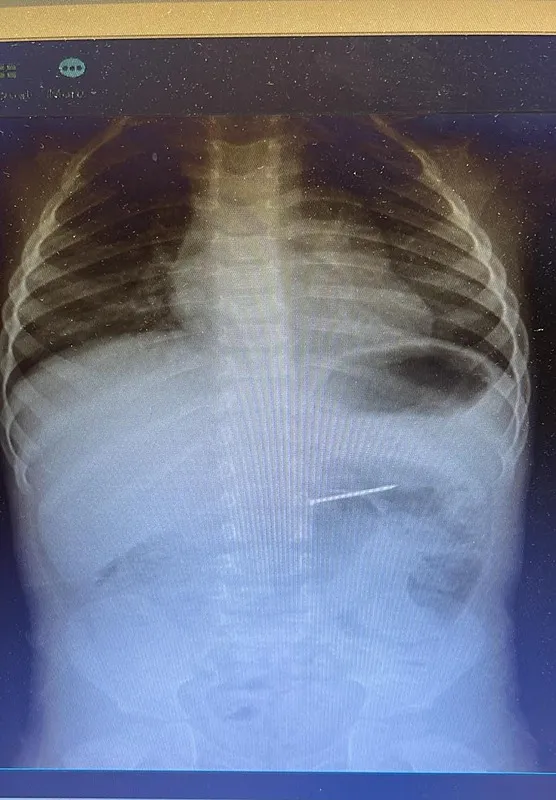

Burdur'un Bucak ilçesinde yaşayan 2 yaşındaki bir çocuk, yuttuğu çivi nedeniyle ailesi tarafından acil sağlık ekiplerine bildirildi. 112 Acil Servis aracılığıyla Süleyman Demirel Üniversitesi (SDÜ) Hastanesi'ne sevk edilen çocuk, Çocuk Gastroenteroloji ve Endoskopi Birimi'nde değerlendirmeye alındı. Radyolojik inceleme sonucu yaklaşık 4 santimetre uzunluğundaki çivinin midedeki konumu tespit edildi ve hemen endoskopik müdahale yapıldı. Yapılan işlemle çivi, herhangi bir komplikasyona yol açmadan başarılı şekilde çıkarıldı. Hasta, kısa süreli gözlem amacıyla serviste takip altına alındı ve sağlık durumu stabil şekilde taburcu edildi.